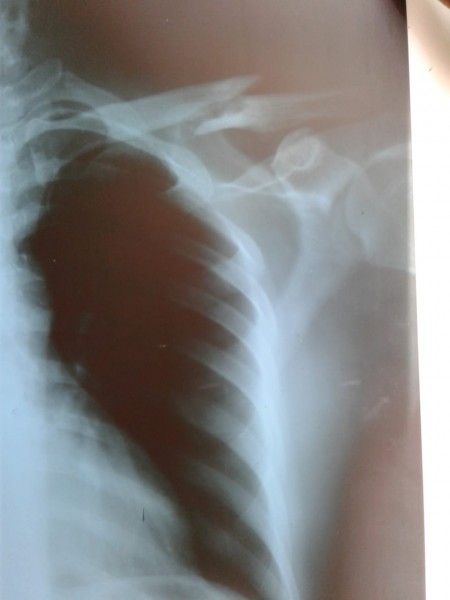

Taveras fue diagnosticado con fracturas en la clavícula y otras partes del cuerpo, al tiempo que denuncia se llevaron toda la mercancía de su local comercial.